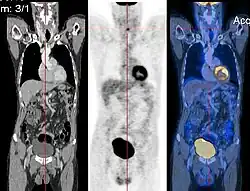

Bildregistrierungsverfahren sind vor allem in der medizinischen Bildverarbeitung häufig. Die mit verschiedenen bildgebenden Verfahren (Modalitäten) aufgenommenen Bilder werden aneinander angeglichen, um aus ihrer Kombination bessere Erkenntnisse zu gewinnen. Werden z. B. MRT-Bilder, die Weichteilgewebe oder Gehirnstrukturen gut darstellen, mit PET-Bildern überlagert, die bestimmte Stoffwechselprozesse sichtbar machen, kann man nachvollziehen, in welchen Gehirnbereichen bestimmte Stoffwechselprozesse stattfinden. Die Überlagerung wird auch als Bildfusion bezeichnet.